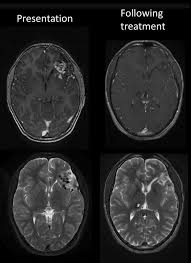

The gadolinium used in the dye is anchored to a molecule to create a nontoxic compound. Indications and usage for dotarem. Proposed the name gadolinium deposition disease for a disease process seen in patients who had normal or near normal function of the kidney but who still developed persistent symptoms of gadolinium toxicity hours to months after these contrast agents were used on them. But gadolinium in gbcas goes through a process called chelation, which makes it safer for use in the body. What is gadolinium contrast medium? There are multiple gadolinium contrast agents used, including gadoterate meglumine, gadobenate dimegluamine, gadodiamide, gadopentate, gadoversetamide, gadobutrol, gadoxetate and others. Serious but rare side effects such as gadolinium toxicity and nephrogenic systemic fibrosis, or nsf, are most often seen in patients with severe kidney problems. 3.0 out of 5 stars.

In 1880, jean charles galissard de marignac studied the. 3.0 out of 5 stars. It occupies the central position in the lanthanide series of elements. Serious but rare side effects such as gadolinium toxicity and nephrogenic systemic fibrosis, or nsf, are most often seen in patients with severe kidney problems. Your provider believes that an mri scan will help doctors diagnose your health condition. Establishing the gadolinium toxicity connection symptoms are generally experienced at an acute level shortly after having a contrast mri and at a chronic level for years following their last contrast mri. Gadolinium was also associated with increases in stillbirths and and neonatal mortality. Gadolinium is primarily eliminated via the kidneys, so exposure.

Classified as a lanthanide, gadolinium is a solid at room temperature. Gbcas are generally thought to be safe to use in patients with good kidney function. The use of gadolinium contrast dyes during pregnancy has been linked to rheumatological, inflammatory and infiltrative skin conditions. Your provider believes that an mri scan will help doctors diagnose your health condition. Gadolinium contrast media (sometimes called a mri contrast media, agents or 'dyes') are chemical substances used in magnetic resonance imaging (mri) scans. The gadolinium levels are also similar across. Routine screening and laboratory testing for renal failure is no longer required prior to the administration of group ii agents. Gbca) for magnetic resonance imaging and computer tomography scanning. It is a strong magnet at room temperature. Establishing the gadolinium toxicity connection symptoms are generally experienced at an acute level shortly after having a contrast mri and at a chronic level for years following their last contrast mri. A landmark research article released in 2016 by semelka et al. The side effects patients are reporting now include joint pain, muscle fatigue and cognitive impairment that can last for years. Gadolinium contrast is also called an mri medium, agent or dye.